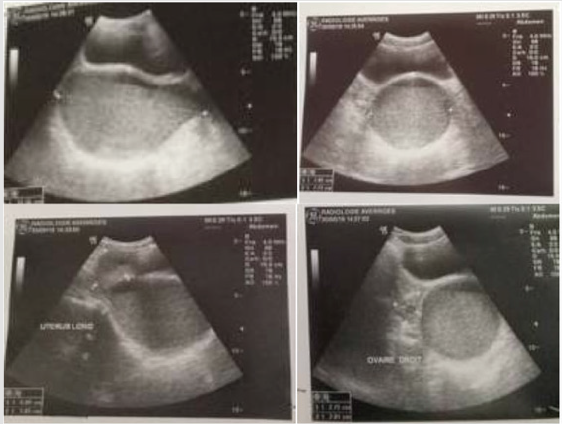

The clinical case is a 14 years old girl with a low social economic level, she had admitted to emergency for abdominopelvic pain, she had no medical history. there is no signs of urinary tract or digestive problems. General examination Find a conscious patient who is hemodynamically stable. Abdominal examination find A flexible abdomen with the presence of a right prlvic mass right which measerd about 10 cm in its large diameter without hepatosplenomegaly. Gynecological examination find A good development of the external genitalia, and secondary sex characteristics. An imperforate and bulging hymen, The rectal examination combined with the abdominal palpation reveals the existence of a soft, sensitive pelvic-abdominal mass varying in size from 8 to 12 cm. a pelvic ultrasound performed which revealed: A homogeneous uterus in the normal place measuring 6cm*4.7cm, with a regular outline. The intrauterine emptiness line is clearly visible, containing a hematometry slide. In the vaginal region: we note the presence of a voluminous oblong image, of thick content measuring 122*78*77mm.Both ovaries are normal in size, measuring 27*20mm at right and 22*15 on the left, and normal looking. The bladder is thin-walled alithiasis; The liver, spleen and both kidneys are free from abnormalities. The diagnosis of hematocolpos was confirmed and the patient undergone a surgical treatment under general anesthesia, the intervention consists of A Y-shaped incision at the hymen to avoid the urethra. The drainage brought back 550cc of blackish blood and the Placement of an intra-vaginal bladder catheter. The course was satisfactory, without stenosis. We dilated the orifice once a week for 1 month, then, once / 15 days, then once / month for 3 months. The patient was followed regularly for a year in consultation, then was lost to follow-up (Figures 1 & 2).

Figure 2: Suprapubic ultrasound: aspects in favor of a hematocolpos: oval collection of retrovesical fluid which communicates above with a normal size uterus.

Figure 3:

A. Axial Suprapubic ultrasound: presence of a retrovesical, median, hypoechoic fluid formation containing a fine echogenic stippling

B. Sagittal section: the collection communicates at the top with the uterine cavity which is not distended.